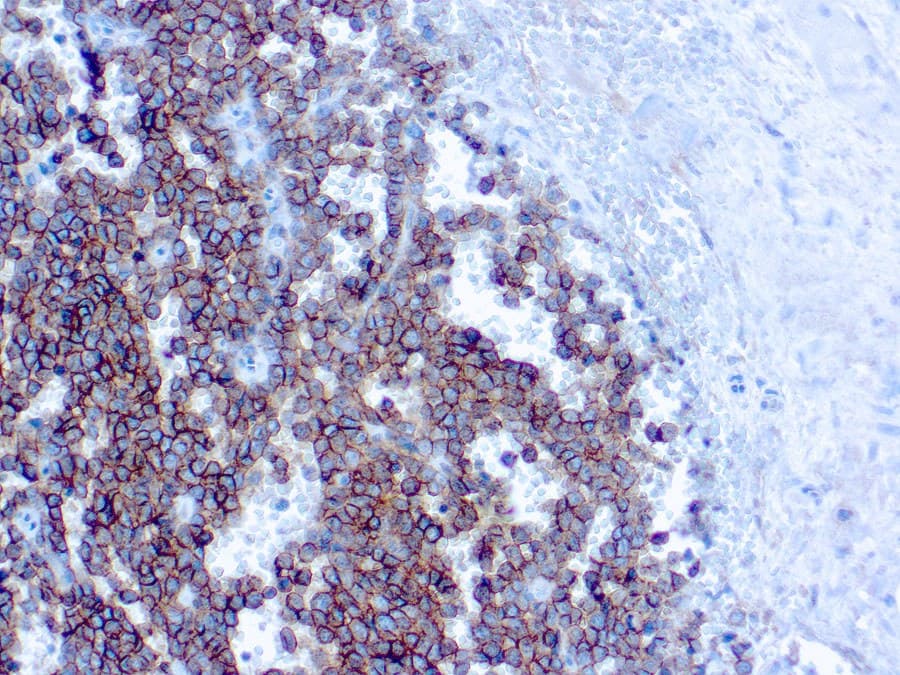

O aglomerado de diferenciação 99 (CD99), também conhecido como MIC2 ou glicoproteína de superfície de células T E2, é uma proteína transmembrana glicosilada expressa por linfócitos, timócitos corticais, células granulosas do ovário, células de ilhotas pancreáticas, células de Sertoli, e células endoteliais. CD99 é uma proteína transmembrana de cadeia única do tipo I, desprovida de sítios de glicosilação ligados ao N que é codificada pelo gene pseudoautosomal MIC2. O CD99 tem um peso molecular aparente de 32 kD e é amplamente expresso numa variedade de tecidos. Está envolvido na adesão de células T, migração leucocitária e diferenciação de célula neuroectodérmica primitiva. O CD99 produz padrões de coloração difusa da membrana em quase todos os sarcomas de Ewing e tumores neuroectodérmicos periféricos primitivos. O CD99 pode ser encontrado no sarcoma sinovial, carcinoma neuroendócrino, leucemia mielóide aguda, condrossarcoma mesenquimal, linfoma linfoblástico, pequenos tumores de células azuis redondas, tumores fibrosos solitários, tumores vasculares, e sarcoma mielóide e produz padrões de coloração heterogéneos, que devem ser acompanhados por outra coloração de anticorpos para um diagnóstico final.